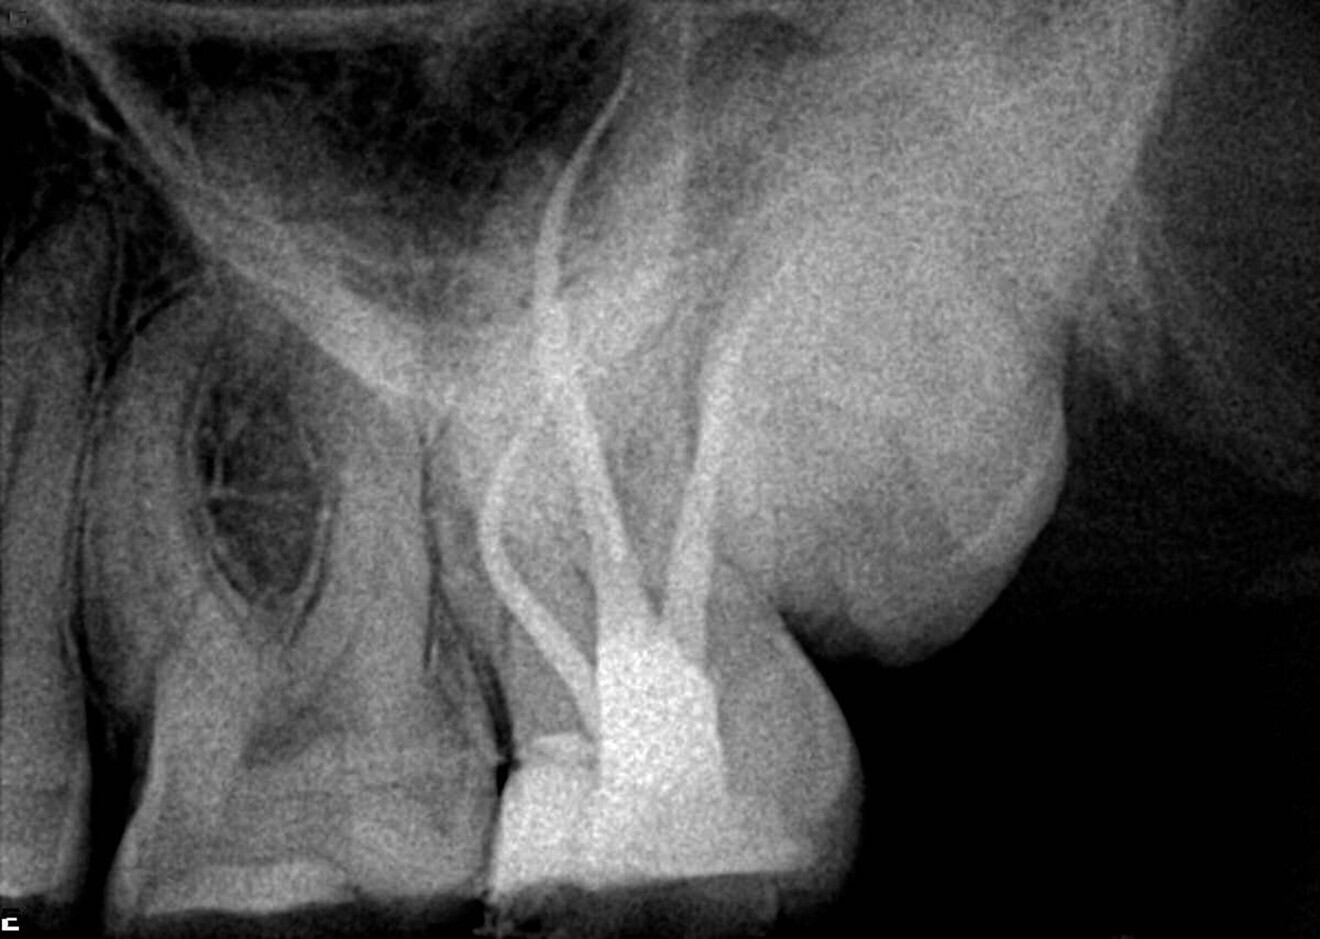

In this first example, the patient was referred for treatment of a sinus tract of the anterior maxilla (Fig. 1). A gutta-percha cone was placed inside the fistula, showing the way to the infection site. This was a straightforward case, prepared using the 25/0.08 Traverse file in the upper part, followed by a 10 K-File (Kerr) to determine the working length and then a 40/0.06 Traverse file taken to working length. Naturally, treatment involved complete chemical preparation and 3D sealing of the root canal space (Fig. 2).

Fig. 1

Fig. 2